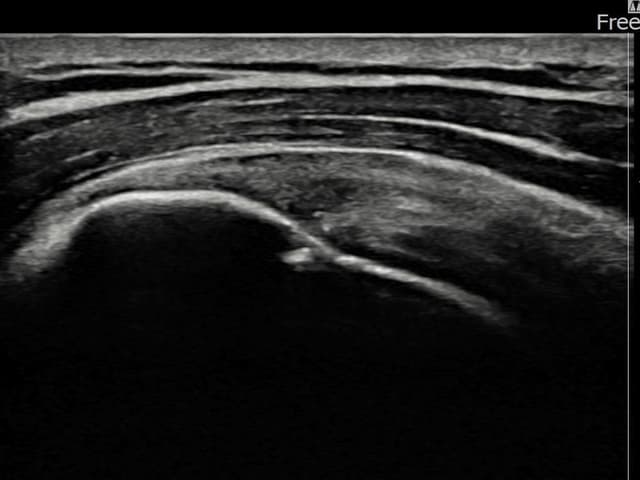

[経過期間: 24.01.25~24.04.03]

[縫縮術] 超音波検査にて左 棘上筋腱 付着部部分断裂(5mm × 3mm (腱厚の約25%欠損))を確認。縫縮術施行後、腱の連続性が回復し、日常生活に復帰されました。